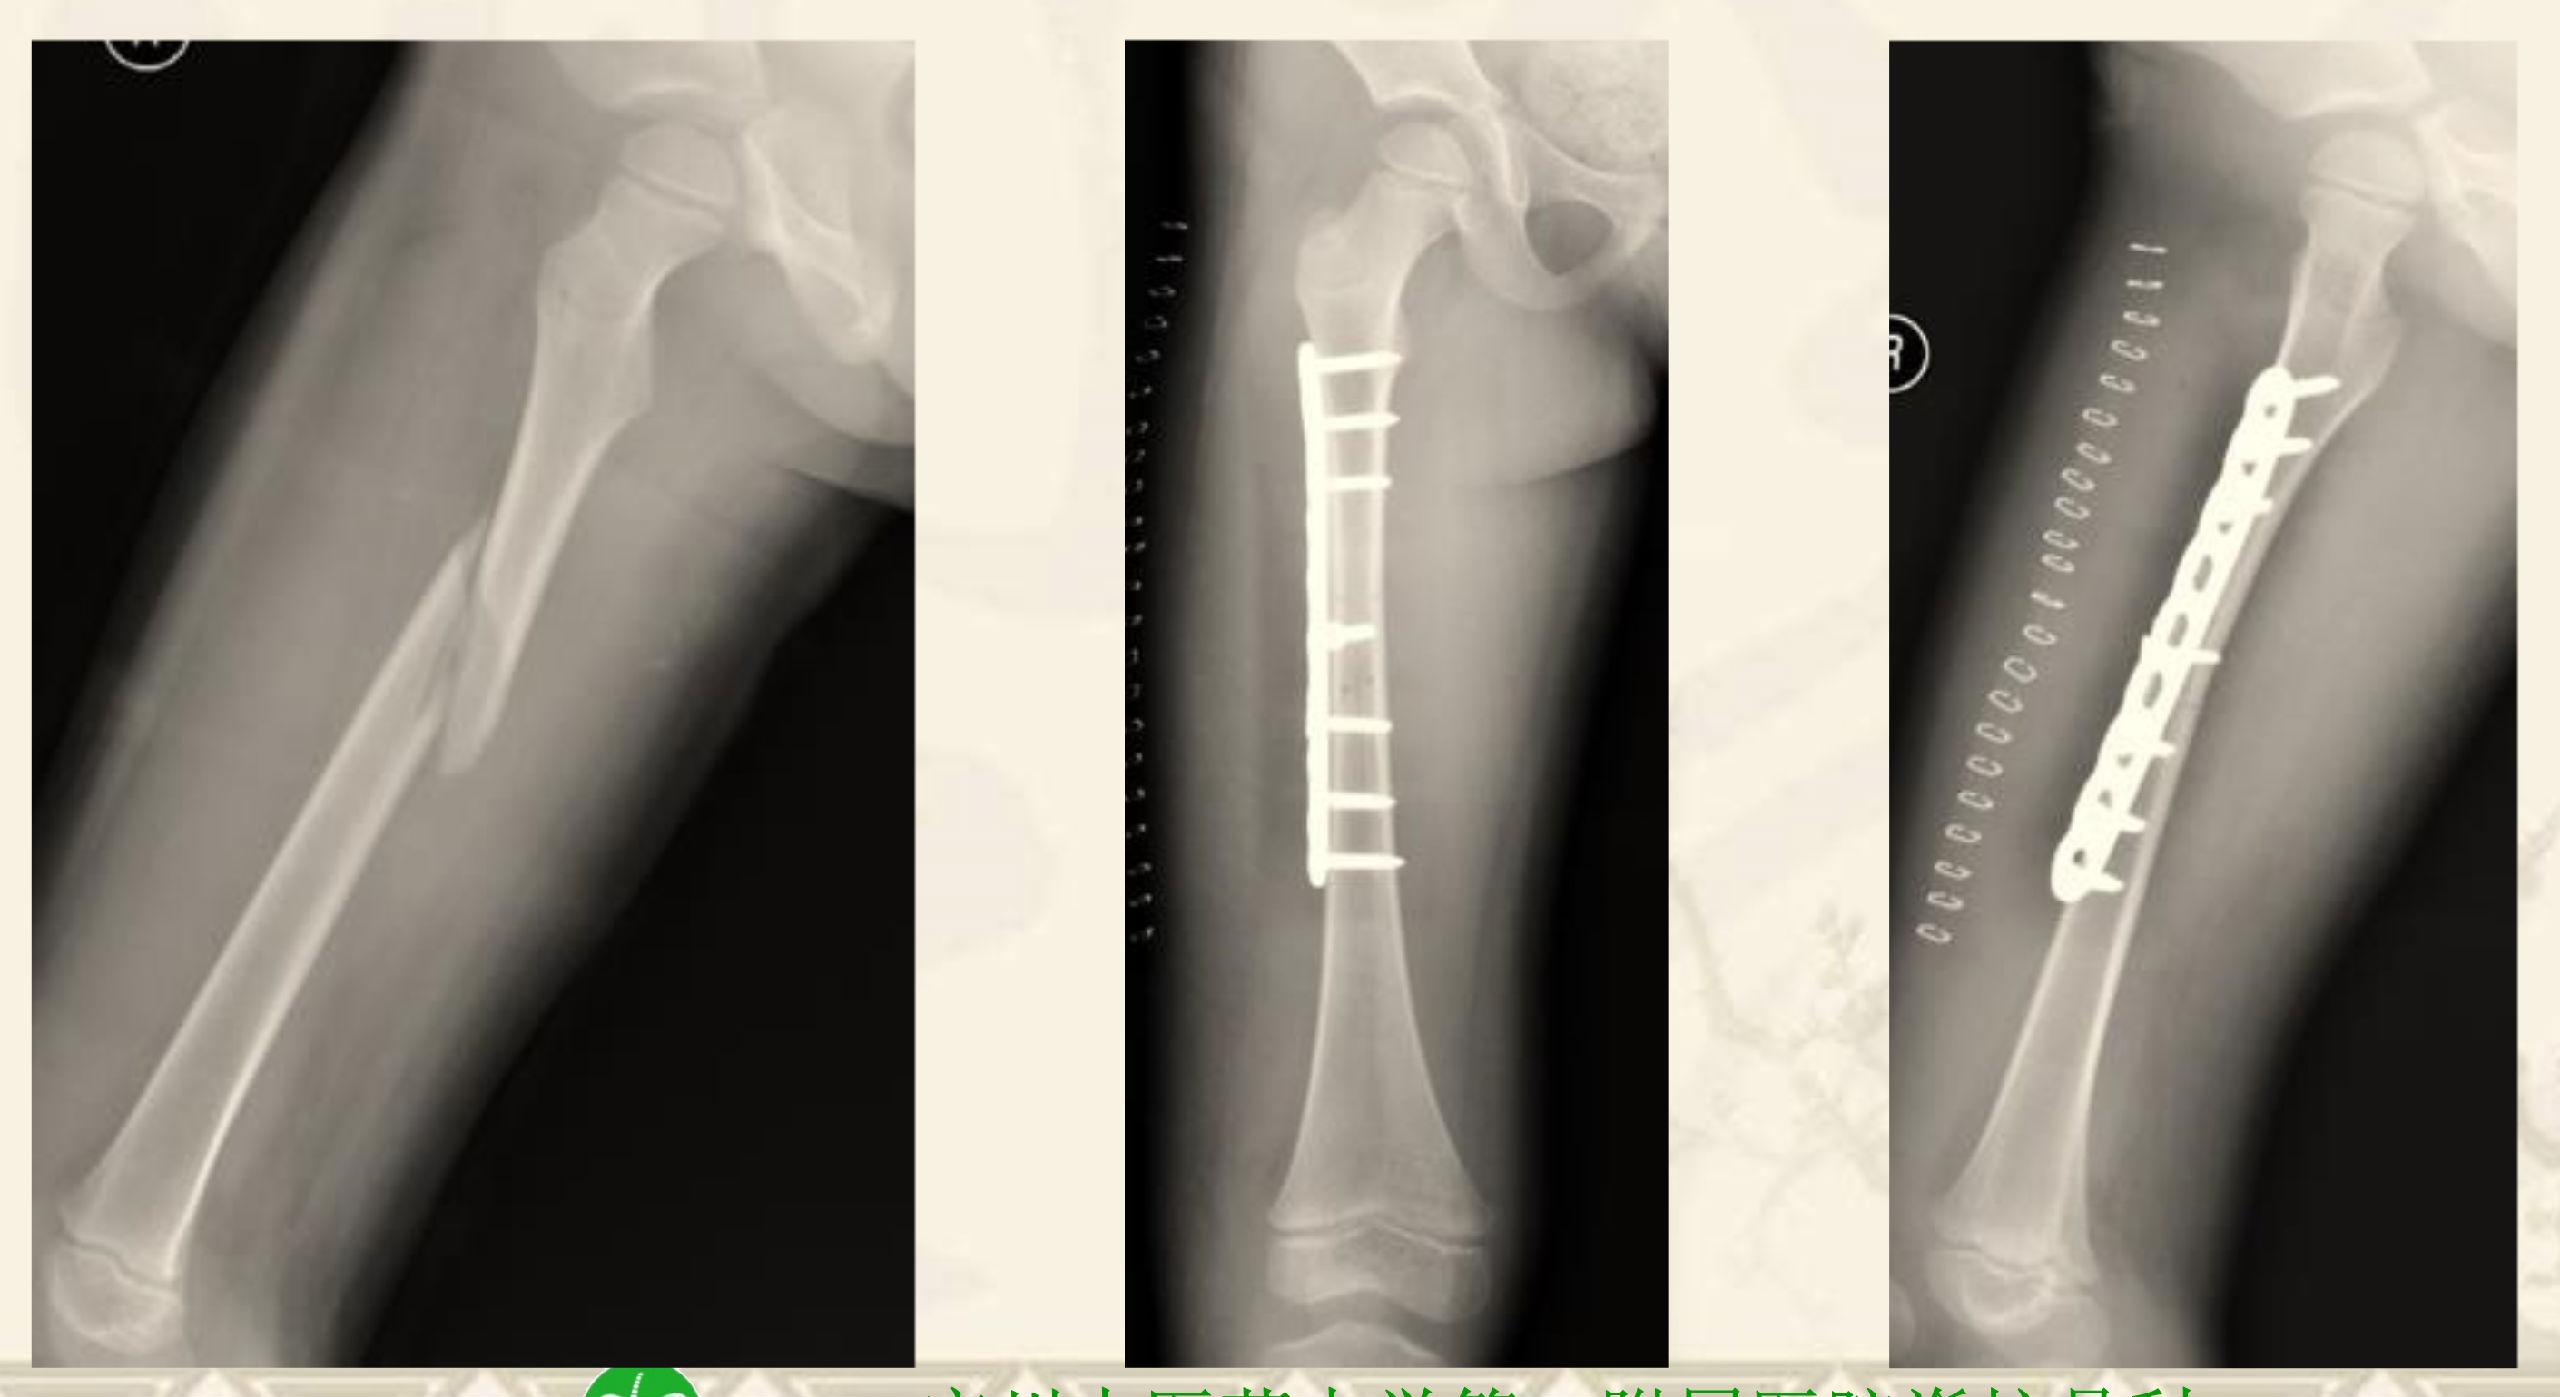

CASE 1

患者T12 OVCF VAS:8分 ODI:75%

骨水泥在骨折区填充不佳,术后疗效欠佳

非手术治疗 1Y Post 塌陷 畸形愈合

CASE 2

患者1月前行PVP,术后VAS:7分,ODI:70%

右侧PVP翻修劶,VAS:2分 ODI:25%